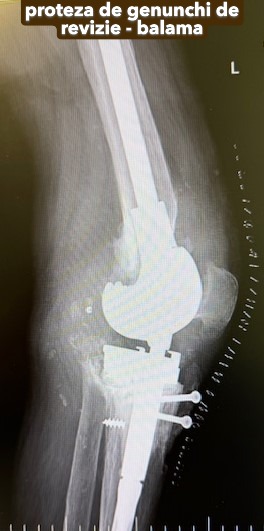

Artroplastia totală de genunchi

Artroplastia totală de genunchi constă în înlocuirea în totalitate a articulației cu o proteză cimentată, care, în prezent, este tot mai performantă.

În funcție de degradarea articulației și de calitatea țesutului osos, pot fi necesare anumite componente suplimentare: augmenturi sau stem tibial.

Dacă genunchiul este instabil, se recomandă protezele stabilizate: LCCK sau balama.

Galerie imagini cu proteze șold și genunchi tratate de dr. Chitea Claudiu Daniel